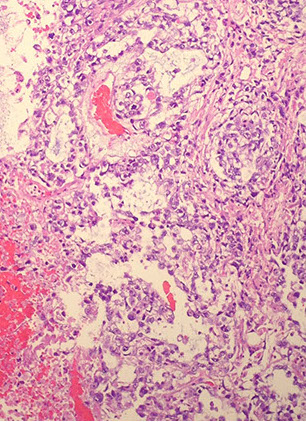

Granulomatous orchitis seen in middle-aged dudes c nut pain and possible fever

- nut looks big and nodular

Micro: granulomas restricted to seminiferous tubules